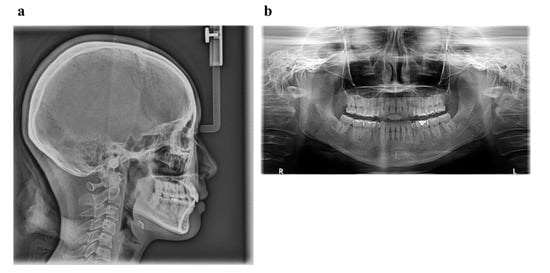

6.1. Diagnosis

6.2. Treatment Objectives

6.3. Treatment Alternatives

6.4. Treatment Progress

| Measurement | Normal (Japanese Woman) | Pretreatment (29 y 19 m) | Posttreatment (31y 2m) |

|---|---|---|---|

| SNA (° ) | 81.3 ± 2.7 | 80.0 | 80.0 |

| SNB (° ) | 78.6 ± 2.7 | 79.5 | 79.0 |

| ANB (° ) | 2.6 ± 1.1 | 0.5 | 1.0 |

| FMA (° ) | 26.3 ± 4.1 | 24.0 | 24.0 |

| FMIA (° ) | 56.9 ± 6.4 | 52.0 | 61.0 |

| IMPA (° ) | 96.8 ± 6.4 | 104.0 | 95.0 |

| U1-FH (° ) | 112.1 ± 4.2 | 126.5 | 115.5 |

| U1-L1 (° ) | 123.5 ± 5.5 | 105.0 | 125.0 |

| U1-A-Pog (mm) | 6.2 ± 1.5 | 11.2 | 4.6 |

| L1-A-Pog (mm) | 3.0 ± 1.5 | 8.1 | 2.3 |

| Gonial angle (° ) | 118.8 ± 6.1 | 117.5 | 117.5 |

| E-line: Upper (mm) | 1.4 ± 2.0 | −0.5 | −2.0 |

| E-line: Lower (mm) | 1.4 ± 2.0 | +0.3 | −0.7 |